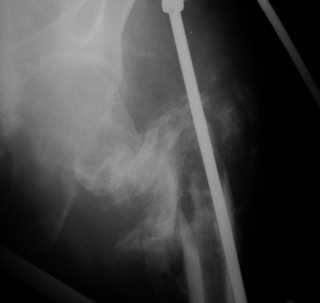

Вот снимки по свежей ситуации, парень 19 лет, длинный оскольчатый перелом бедра от шейки до в-с/3. давно уже ходит на своих ногах.

Делалось не мной (ассистировал), я на тазах "пока ещё не волшебник, а только учусь"

Представленные Вами рентгенограммы действительно являются примером качественной фиксации спице-стержневым аппаратом. Они, как ни что другое, многое иллюстрируют.

Кроме того, было бы ошибкой ставить знак равенства между нашим и Вашим пациентами. Они не только не похожи, разница между ними просто огромная. Говорю это не для того, чтобы задеть Вас или обидеть. Ни в коем случае. Просто теперь я понимаю, что Ваше мнением строится на простом преломлении Ваших подходов к лечению пациентов со свежими переломами, на ситуацию, абсолютно несопоставимую, подобную нашей.